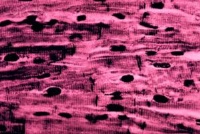

心肌细胞与骨骼肌的结构基本相似,也有横纹,但在结构上具有以下几个特征:

①心肌细胞为短柱状,一般只有一个细胞核,而骨骼肌纤维是多核细胞。心肌细胞之间有闰盘结构。该处细胞膜凹凸相嵌,并特殊分化形成桥粒,彼此紧密连接,但心肌细胞之间并无原生质的连续。心肌组织过去曾被误认为是合胞体,电子显微镜的研究发现心肌细胞间有明显的隔膜,从而得到纠正。心肌的闰盘有利于细胞间的兴奋传递。这一方面由于该处结构对电流的阻抗较低,兴奋波易于通过;另方面又因该处呈间隙连接,内有15~20埃的嗜水小管,可允许钙离子等离子通透转运。因此,正常的心房肌或心室肌细胞虽然彼此分开,但几乎同时兴奋而作同步收缩,大大提高了心肌收缩的效能,功能上体现了合胞体的特性,故常有“功能合胞体”之称。

②心肌细胞的细胞核多位于细胞中部,形状似椭圆或似长方形,其长轴与肌原纤维的方向一致。肌原纤维绕核而行,核的两端富有肌浆,其中含有丰富的糖原颗粒和线粒体,以适应心肌持续性节律收缩活动的需要。从横断面来看,心肌细胞的直径比骨骼肌小,前者约为15微米,而后者则为100微米左右。从纵断面来看,心肌细胞的肌节长度也比骨骼肌的肌节为短。